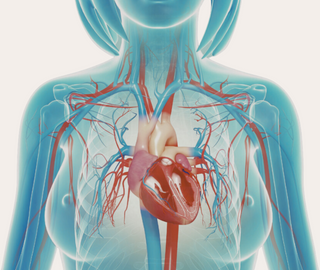

THE VITAL ROLE OF BLOOD FLOW IN PREGNANCY

During pregnancy your body is working harder than you even know. Your heart works 30% harder, and your body creates 50% more blood to deliver oxygen and nutrients to you and your baby through placenta and umbilical cord. Graduated compression leggings and socks are one way to help. Poor circulation and insufficient blood flow can have a number of negative health impacts.